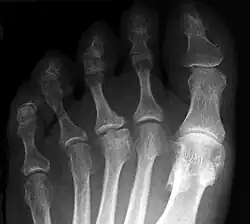

В 1908 году учёный подробно изучил и описал хроническое дистрофическое заболевание ладьевидной кости стопы, приводящее к её асептическому некрозу, которое с того времени стали называть его именем болезнь Келлера I[11][6].

В 1920 году Альбан Кёлер описал остеохондропатию головок плюсневых костей, которая получила название болезнь Келлера II или болезнь Фрейберга–Кёлера[6] (поскольку заметный вклад в её изучение внёс также немецкий врач Альберт Генри Фрейберг[12])[13].